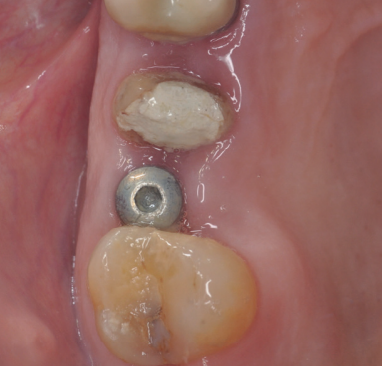

Caso clínico: se presenta el caso clínico de una mujer de 61 años, que acudió a consulta presentando dolor intenso en la zona del segundo premolar superior derecho (1.5). Se realizó la exodoncia del 1.5, usándose como diente donante para realizar una preservación del alveolo tras la extracción. Cuatro meses tras el procedimiento, se colocó un implante y se tomó una biopsia para realizar un análisis histomorfométrico. Un año tras la carga del implante se observaron buenos resultados clínicos y radiográficos.

Clinical case: a 61-year-old woman is presented, who came to private dental clinic presenting intense pain in the area of an upper bicuspid of the first quadrant (1.5). Exodontia of the 1.5 was performed, using it as a donor tooth to obtain the biomaterial to preserve its alveolus. After 4 months re-entry was performed and an implant was placed, harvesting a bone biopsy for histomorphometric analysis. One year post-loading, good clinical and radiographic results were shown.